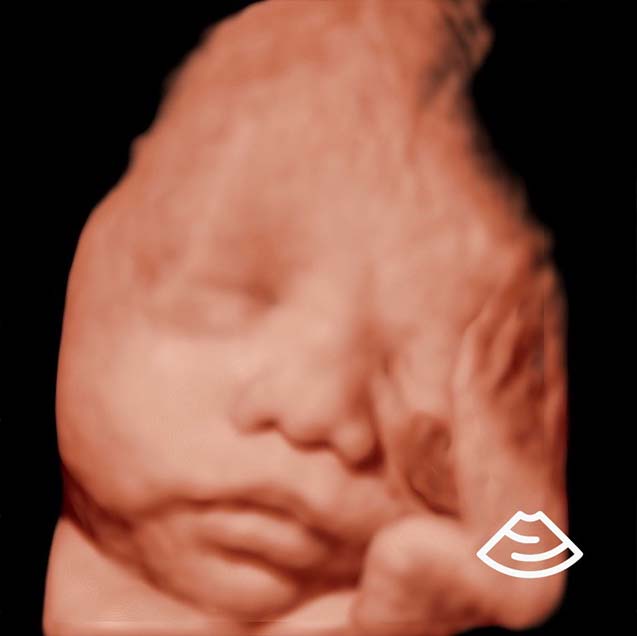

Ultrasonido 3D/4D/5D

La carita de tu bebé como siempre la quisiste ver. Esta modalidad te permitirá conocerlo de una forma más realista y natural.